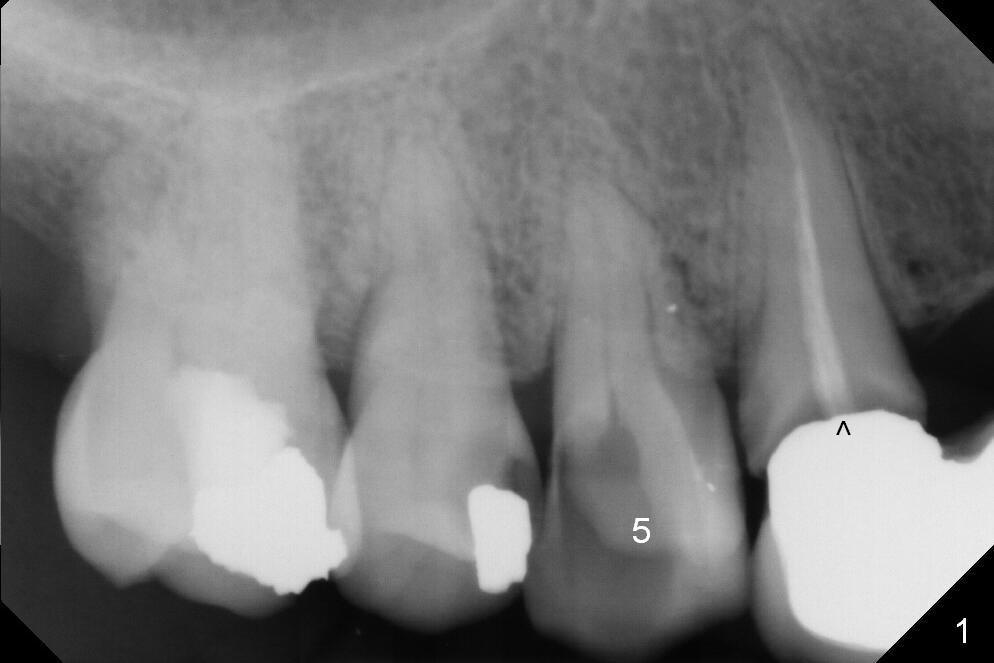

A 43-year-old woman has poor dentition including the tooth #5 (Fig.1) for RCT (Fig.3) and the teeth #2, 30 and 31 are missing.  The retainer at #6 fractures (Fig.1 *).  After sectioning the bridge between #7 and 8, fabricate prefabricated post at #6 if the latter is salvageable.  Otherwise extract (Clindamycin) and implant (Fig.3).  Anyway, a 3-mm or smaller one-piece implant is to be placed at #7 for stability and retention.  Pay attention to the labial concavity at #7 (Fig.2 *).  Surgical stent has been made.